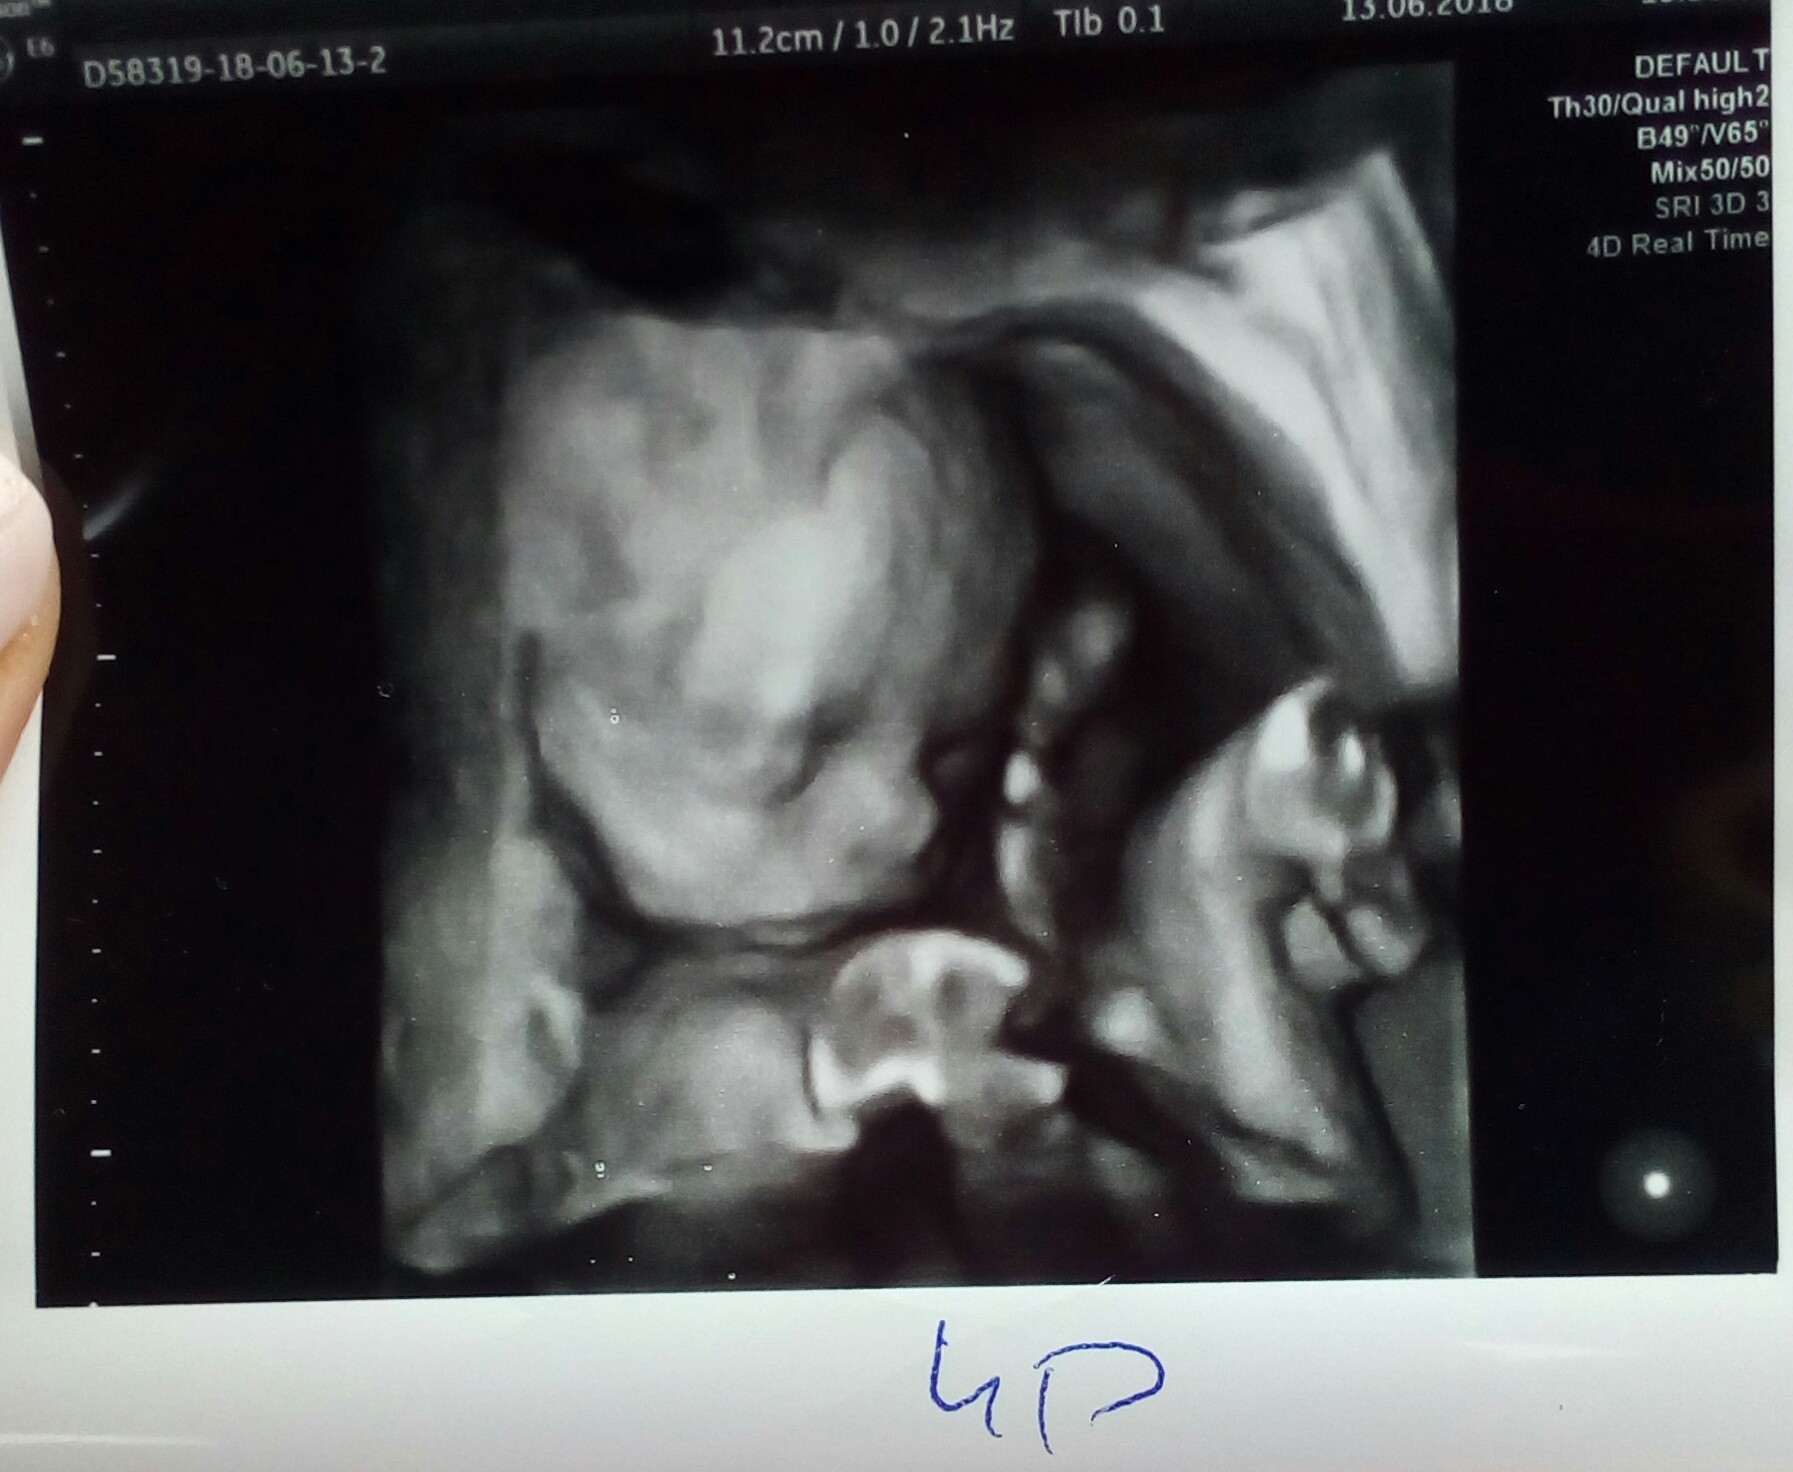

Wizyta prenatalna okey ..potwierdzony ostatecznie chlopak i super ;)Zobacz załącznik 867134